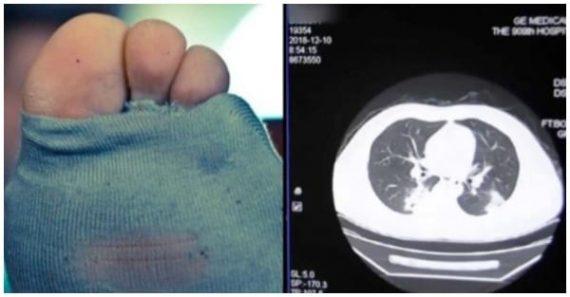

Η ακτινογραφία που υποβλήθηκε απέδειξε πως πάσχει από σοβαρή πνευμονική λοίμωξη και το νοσοκομείο επιβεβαίωσε πως ο λόγος ήταν η συνήθειά του.

Οι γιατροί δεν πίστευαν στα αυτιά τους όταν ο ασθενής τους αποκάλυψε τη βραδινή ρουτίνα του…